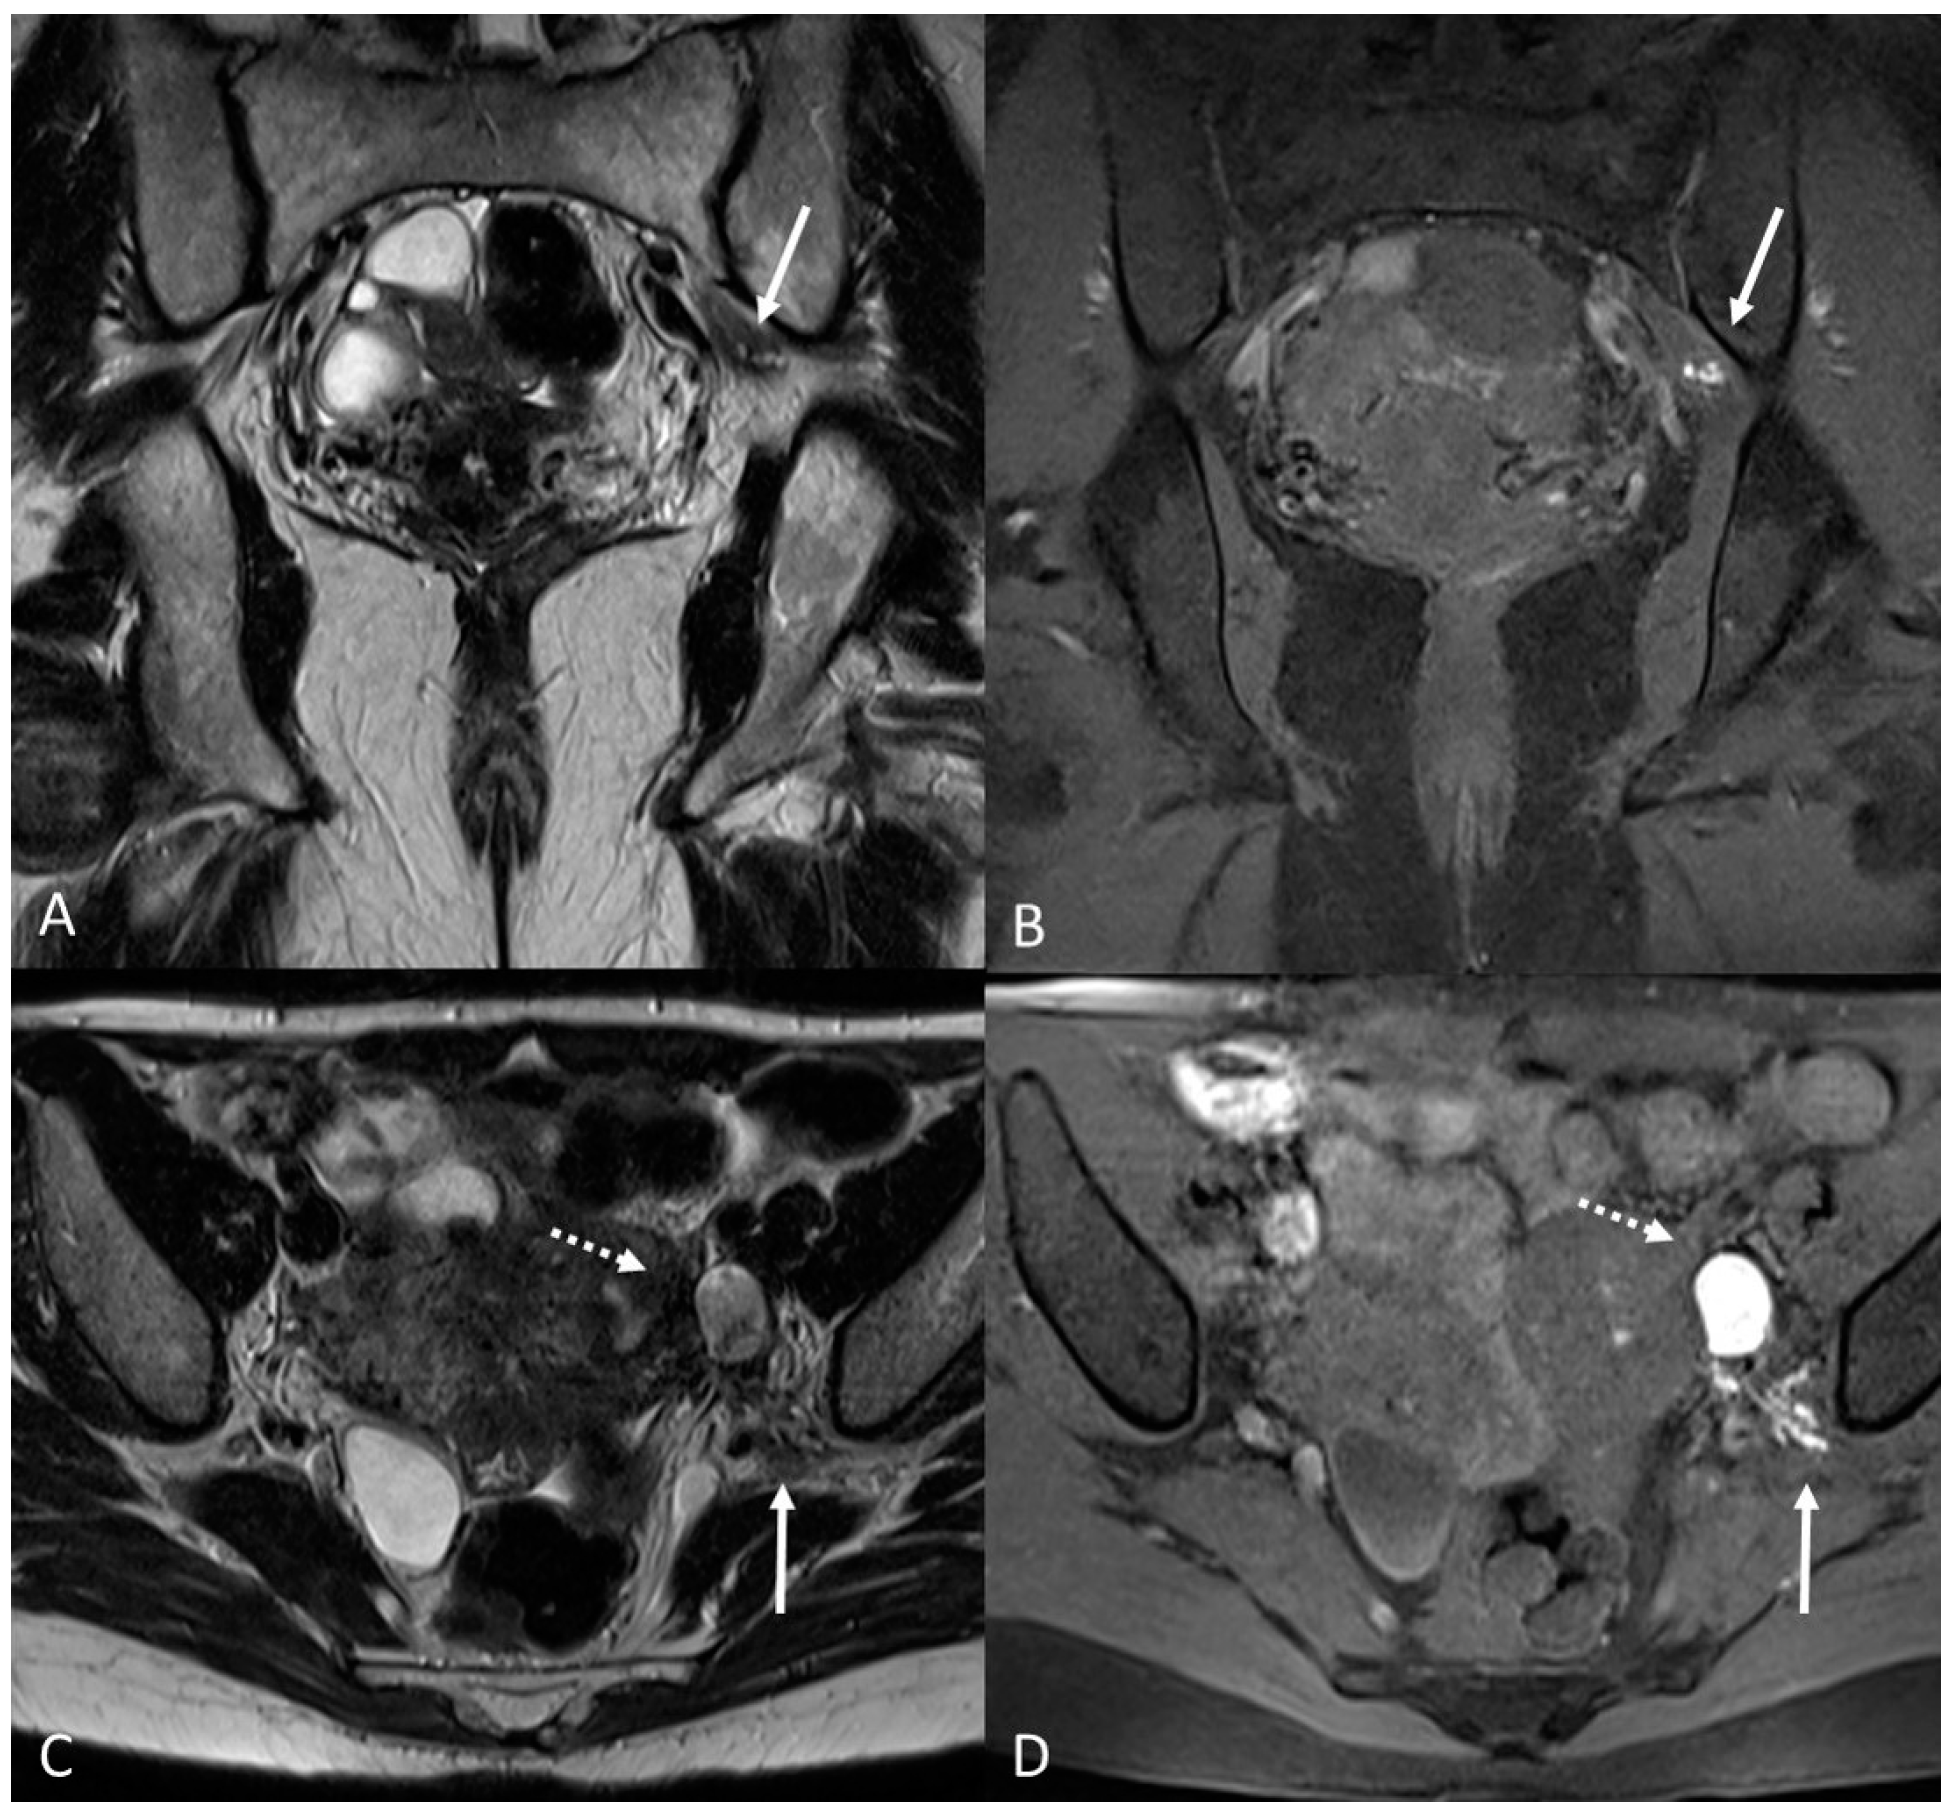

3.2. Deep Infiltrating Endometriosis (DIE)

3.2.3. Torus Uterinus and Sacrouterine Ligaments

3.2.4. Rectovaginal Septum